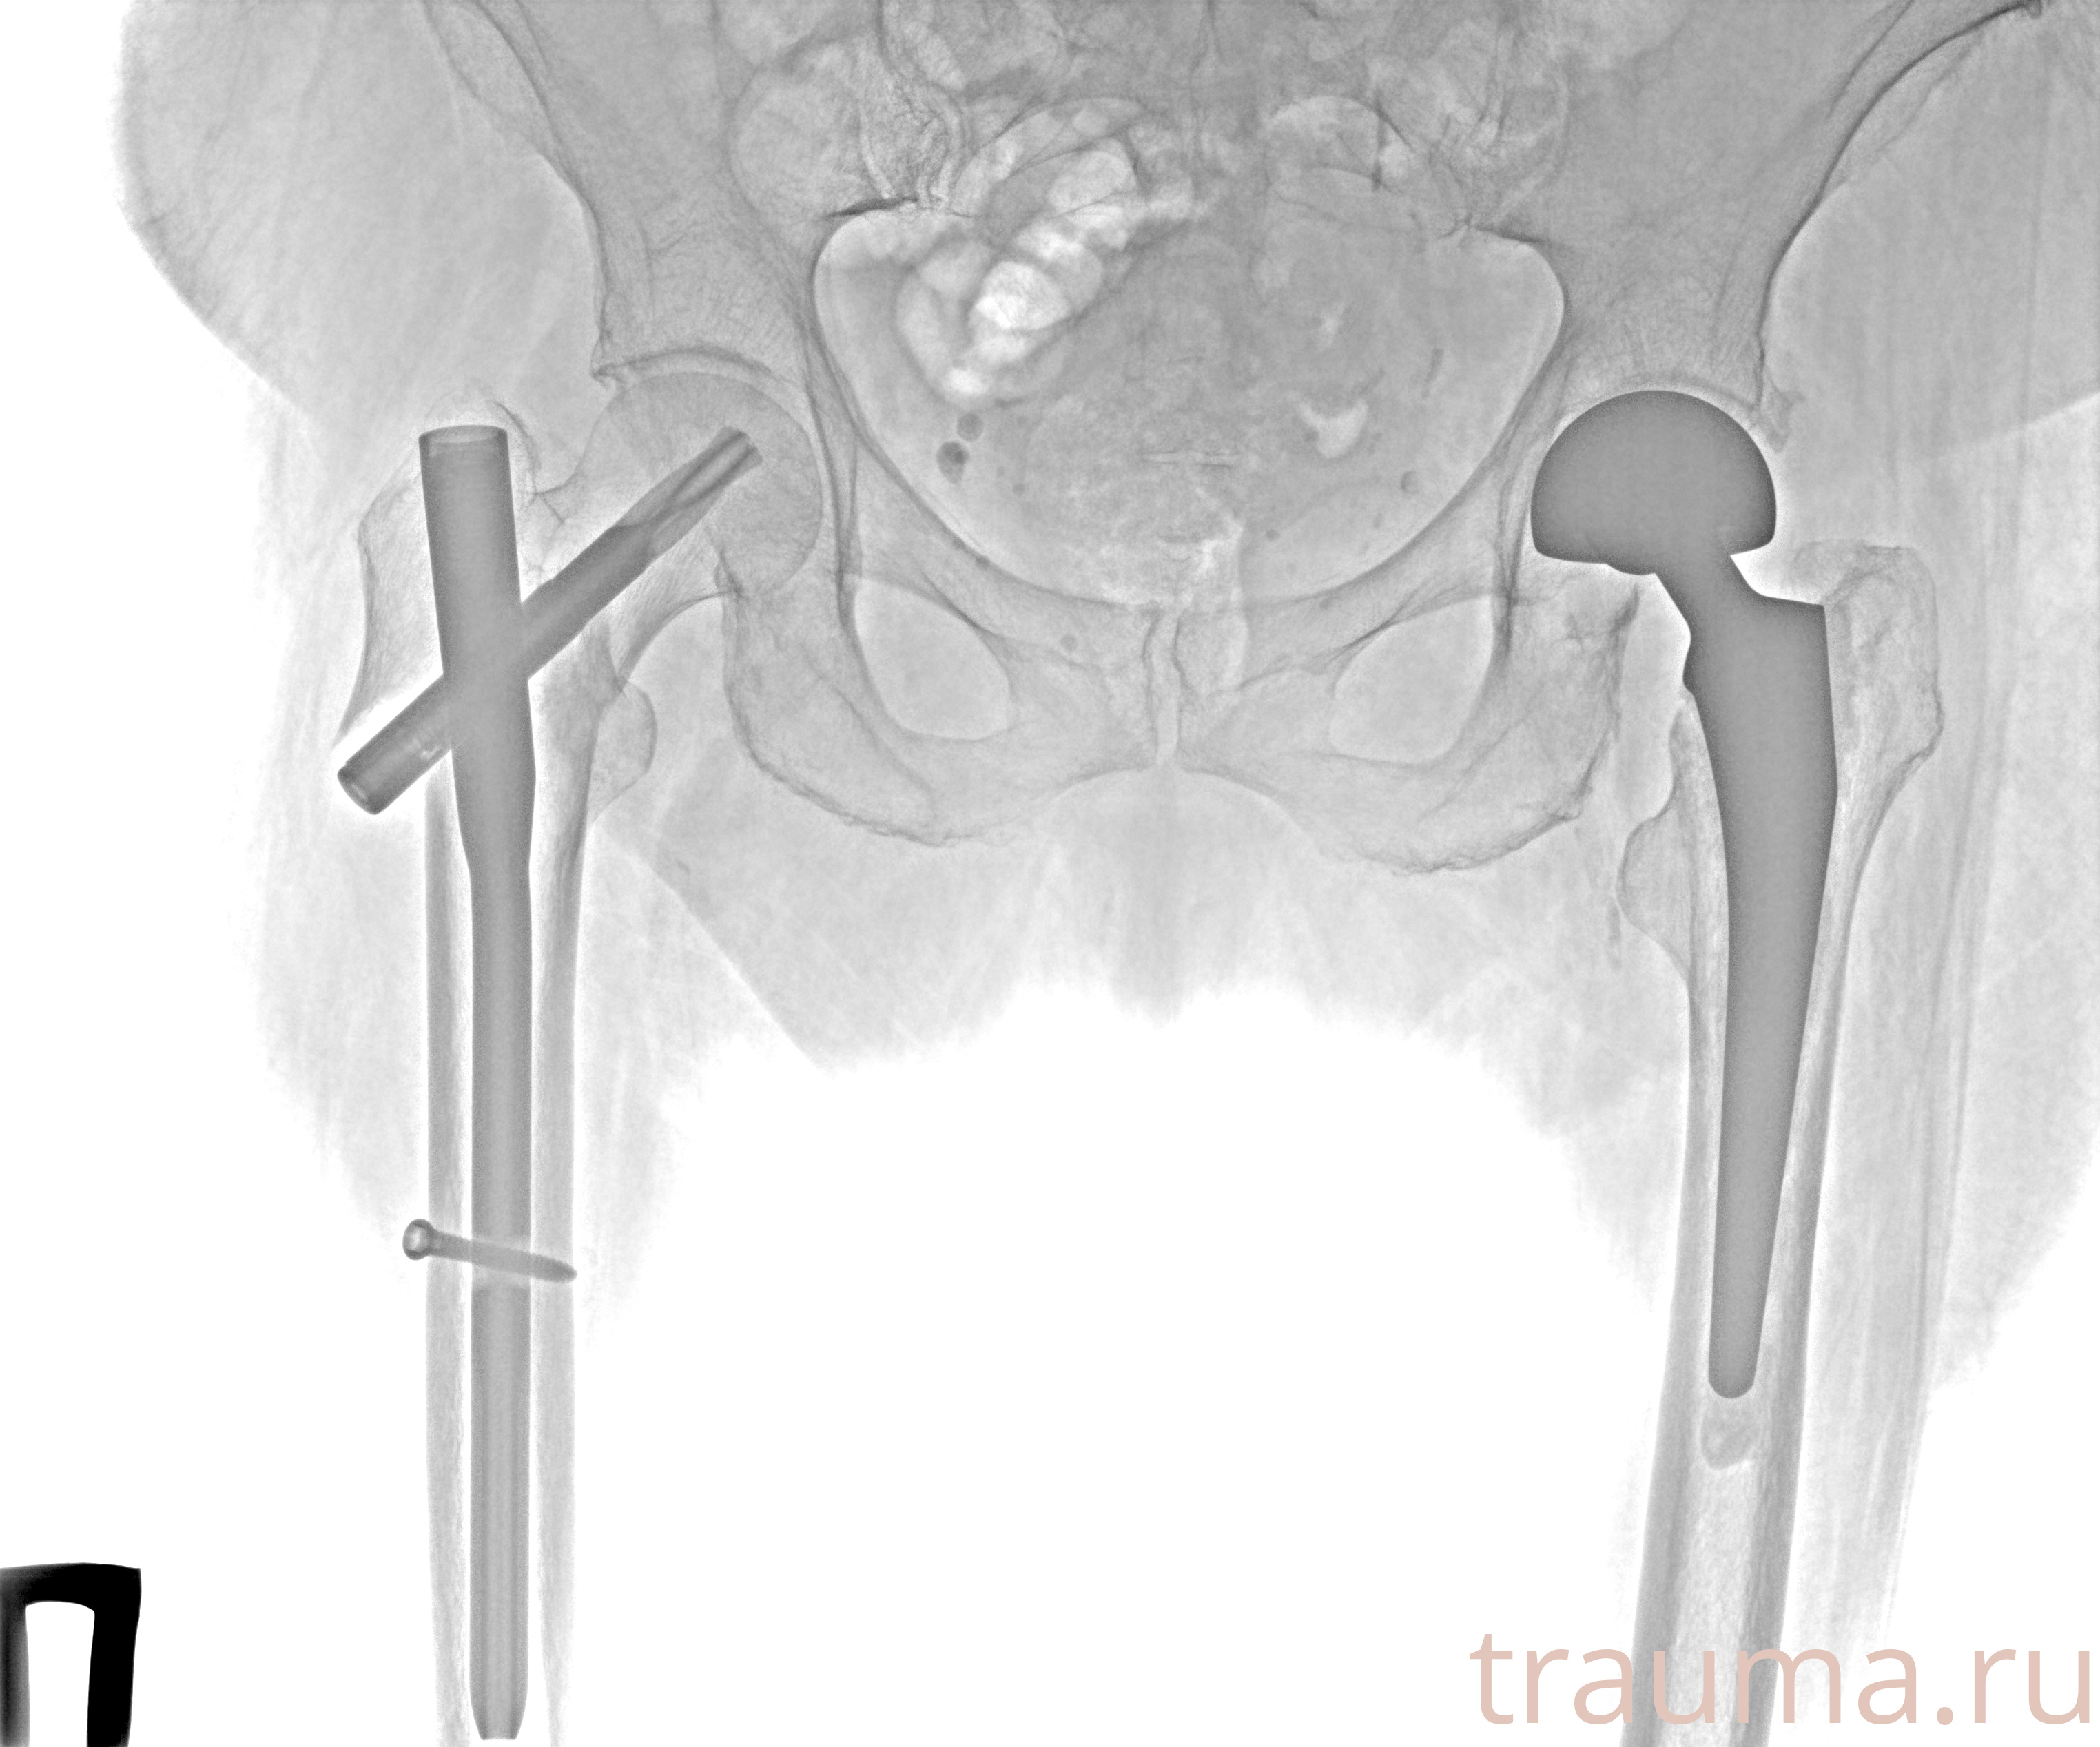

Рентгенограммы

Рентген на дому: по вашему адресу приезжает врач-рентгенолог, травматолог-ортопед с мобильным рентгеновским аппаратом, проводит диагностику травмы или заболевания, делает необходимые рентгенограммы, дает рекомендации по дальнейшему лечению. Получить качественные снимки в домашних условиях возможно благодаря уникальной методике, разработанной МосРентген Центром для института  Склифосовского